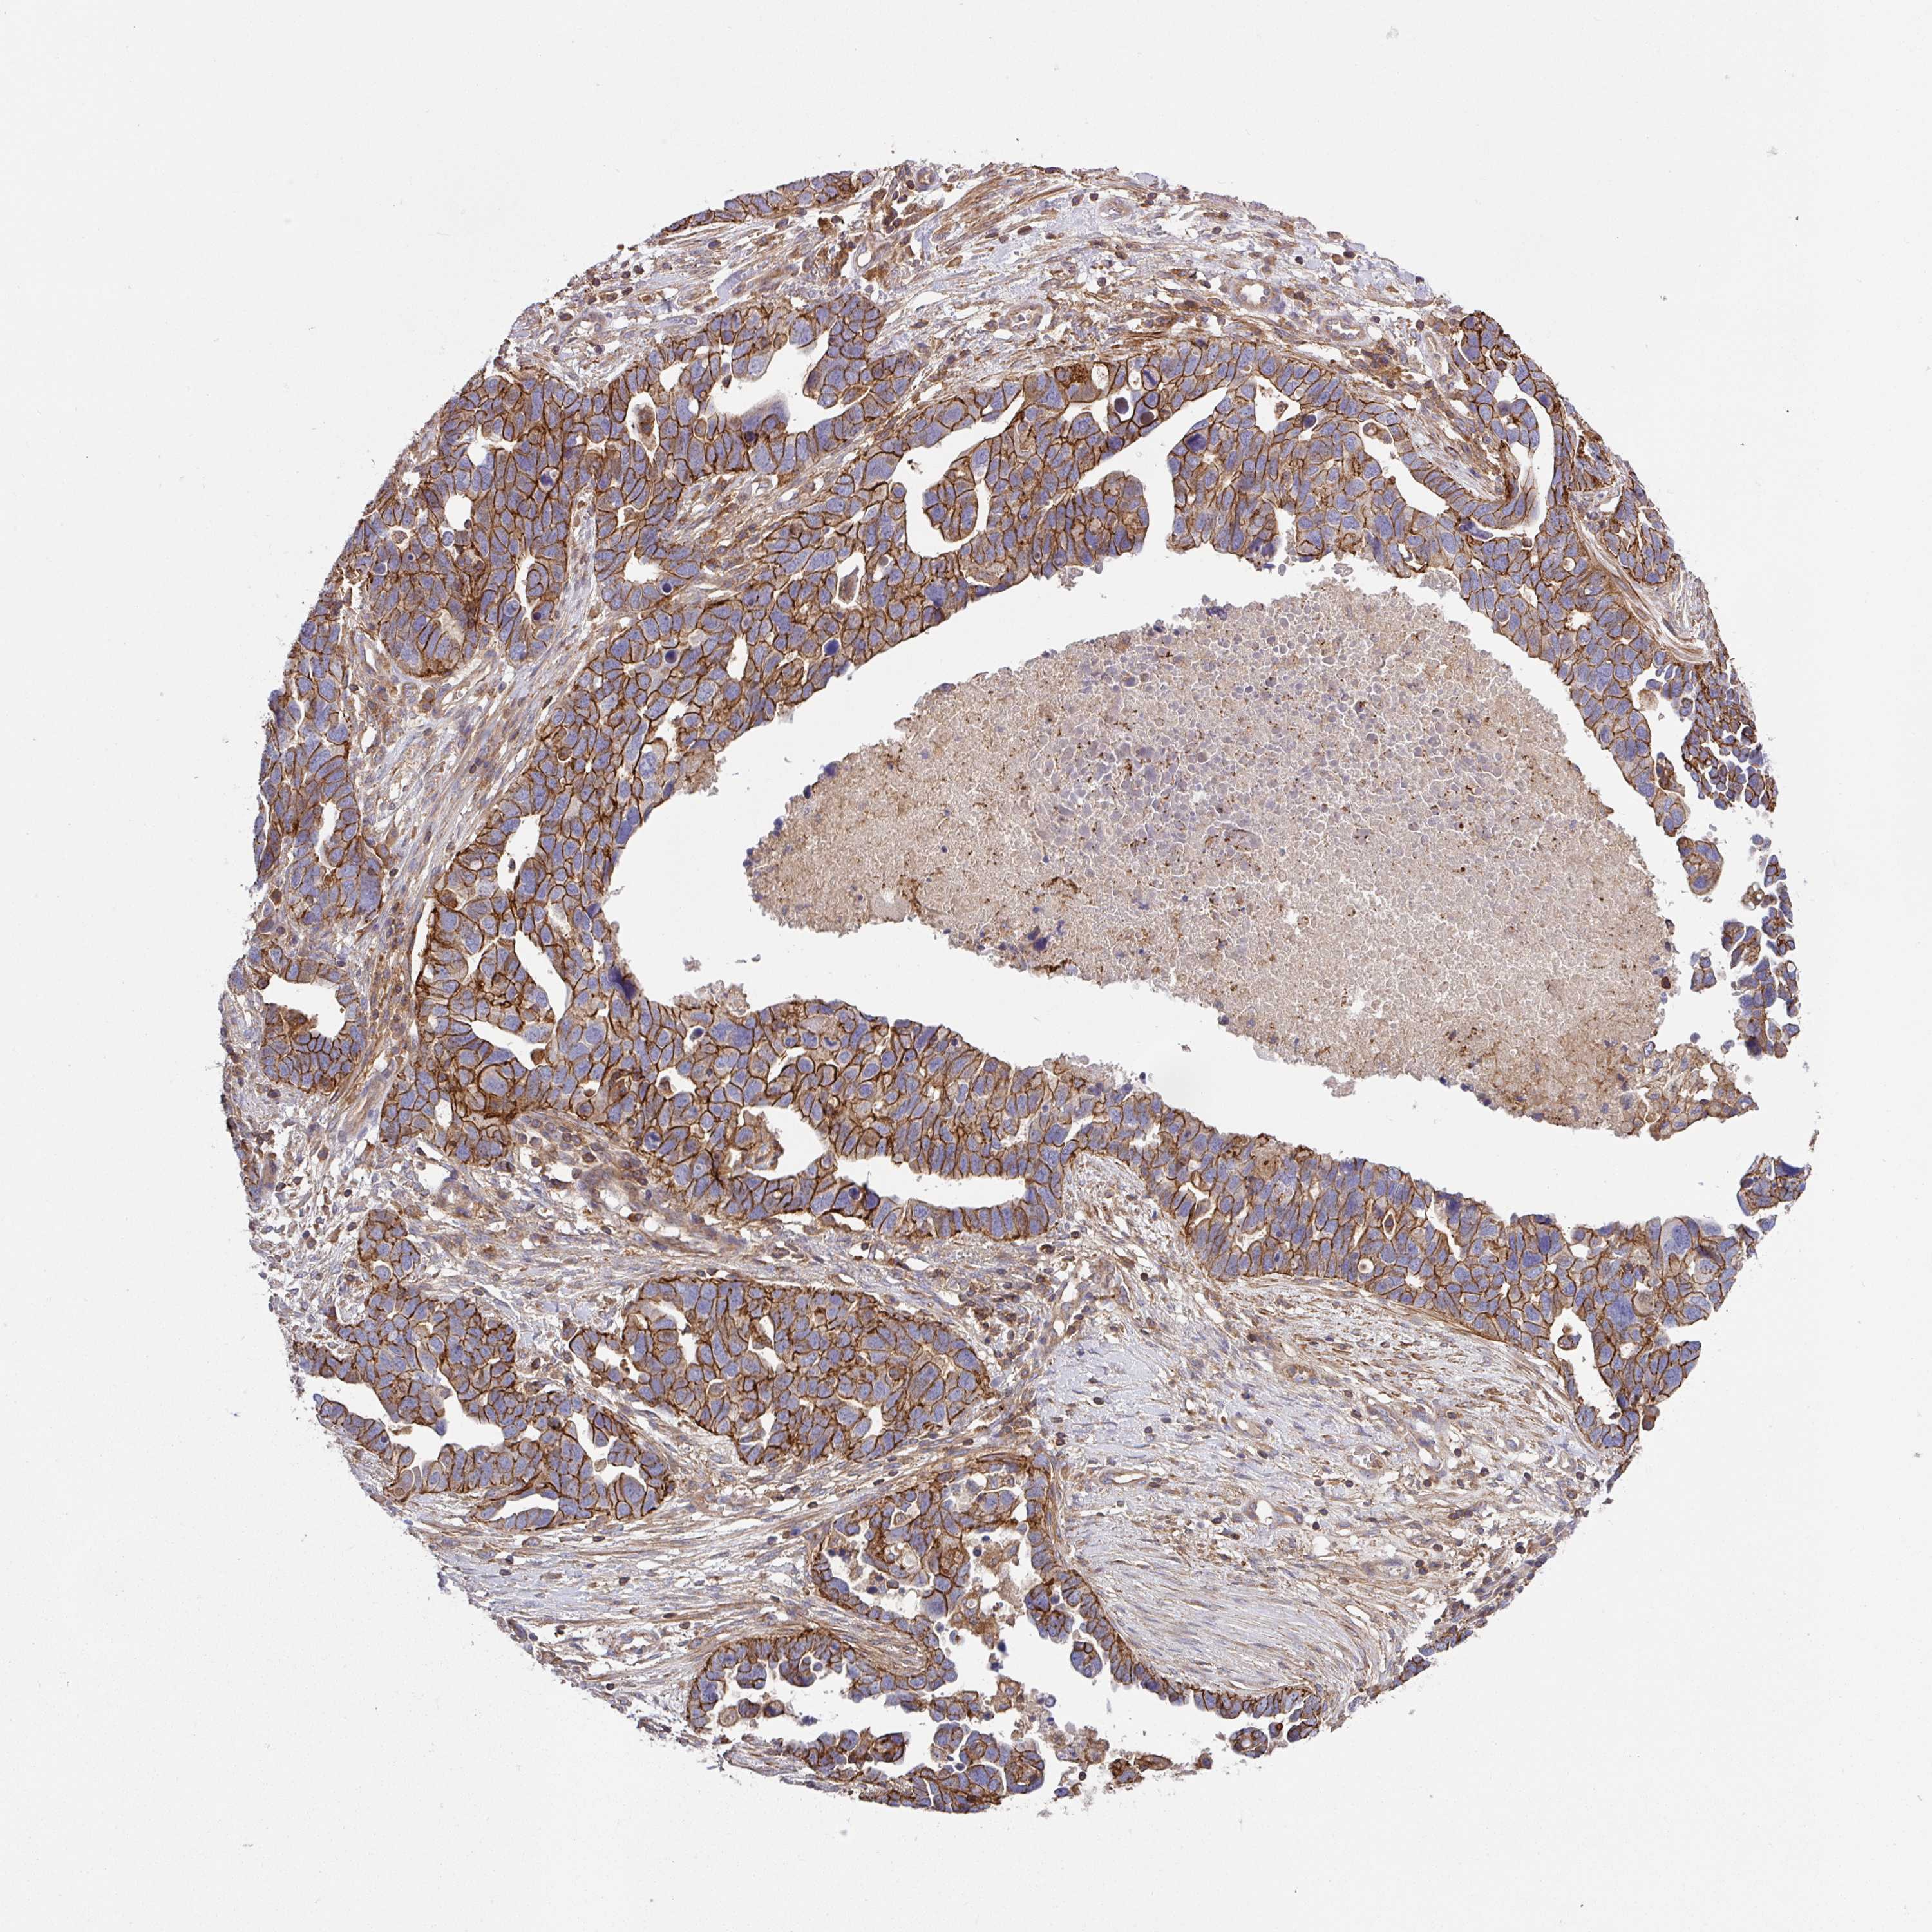

OVARIAN CANCER - Protein expressioni

A mouse-over function shows sample information and annotation data. Click on an image to view it in a full screen mode. Samples can be filtered based on level of antibody staining by selecting one or several of the following categories: high, medium, low and not detected. The assay and annotation is described here.

Note that samples used for immunohistochemistry by the Human Protein Atlas do not correspond to samples in the TCGA dataset.

Antibody stainingi

Antibody staining in the annotated cell types in the current human tissue is reported as not detected, low, medium, or high, based on conventional immunohistochemistry profiling in selected tissues. This score is based on the combination of the staining intensity and fraction of stained cells.

Each image is clickable and will lead to virtual microscopy that enables deeper exploration of all samples and also displays staining intensity scores, fraction scores and subcellular localization as well as patient and tissue information for each sample.

Antibody HPA051578

Staining

High

Medium

Low

Not detected

Intensity

Strong

Moderate

Weak

Negative

Quantity

>75%

75%-25%

<25%

None

Location

Nuclear

Cytoplasmic/membranous

Cytoplasmic/membranous,nuclear

Cystadenocarcinoma, serous, NOS

Carcinoma, NOS

Cystadenocarcinoma, mucinous, NOS

Carcinoma, endometroid